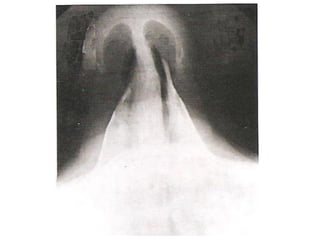

Angiografia do Crânio

• Exame radiográfico após injeção

de contraste;

• Alta densidade tissular não resulta

em resolução de contraste.

   Doenças da substância branca;

   Neoplasias;

   Doenças infecciosas;

   Distúrbios hemorrágicos;

   Distúrbios isquêmicos.